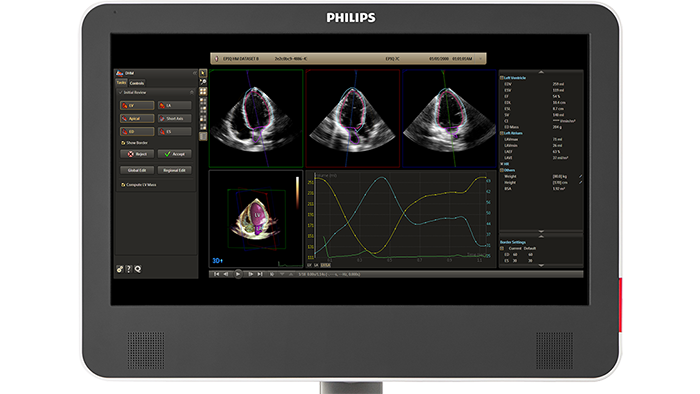

Evolving from Philips HeartModel, Dynamic HeartModel provides more critical capabilities in addition to LV and LA volumes to expand your clinical use and increase diagnostic confidence through 3D echocardiography technology. The Dynamic HeartModel tracks every frame over the cardiac cycle using 3D speckle technology. The moving contours of LA and LV borders and waveforms, additional LV, LA indexes and LV mass measurements provide a holistic view of the left heart function. The LV wall motion and the linkage between the LV and LA volume change over the heart cycle in order to increase your diagnostic confidence. In addition, the multi-beat selection and results average make the heart function evaluation more reliable than single beat, being ideal for arrhythmia or atrial fibrillation patients.

Boost your confidence in cardiac quantification during everyday workflows with HeartModel. This intuitive and validated 3D tool provides robust, reproducible ejection fraction (EF) in just seconds. What’s more, HeartModel is the only validated tool to provide simultaneous LV and LA volumes. It helps you easily characterize LA volume – shown to be an indicator of cardiovascular outcomes – to yield additional clinical information with no extra time or steps.